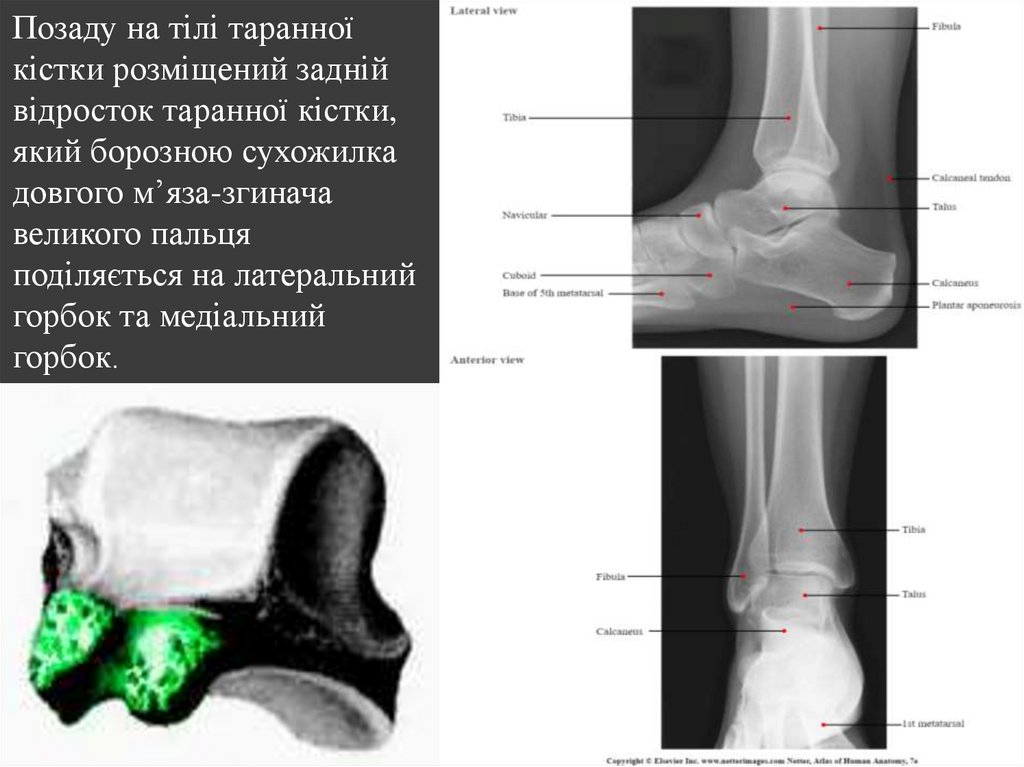

Позаду на тілі таранної

кістки розміщений задній

відросток таранної кістки,

який борозною сухожилка

довгого м’яза-згинача

великого пальця

поділяється на латеральний

горбок та медіальний

горбок.